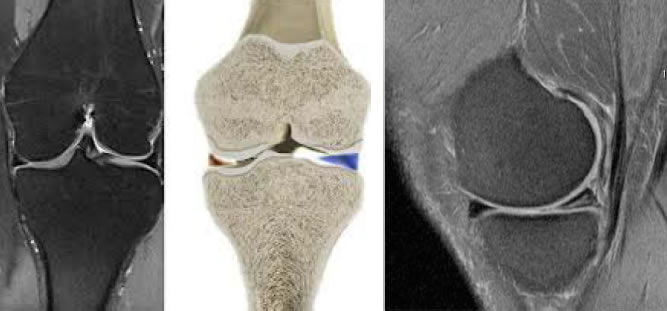

Une technique plus précise comme l'Imagerie par Résonance Magnétique (IRM) permet d'étudier l'état du ligament. L'IRM ne peut être interprétée qu'associée à un bilan complet car le ligament peut avoir un aspect normal alors qu'il ne remplit plus son rôle parce qu'il n'est plus attaché au bon endroit. L'IRM montre aussi très bien d'éventuels problèmes associés : souvent une atteinte des ménisques, ou, très rarement, du ligament croisé postérieur, qui retient le tibia vers l'arrière (IRM en photo).